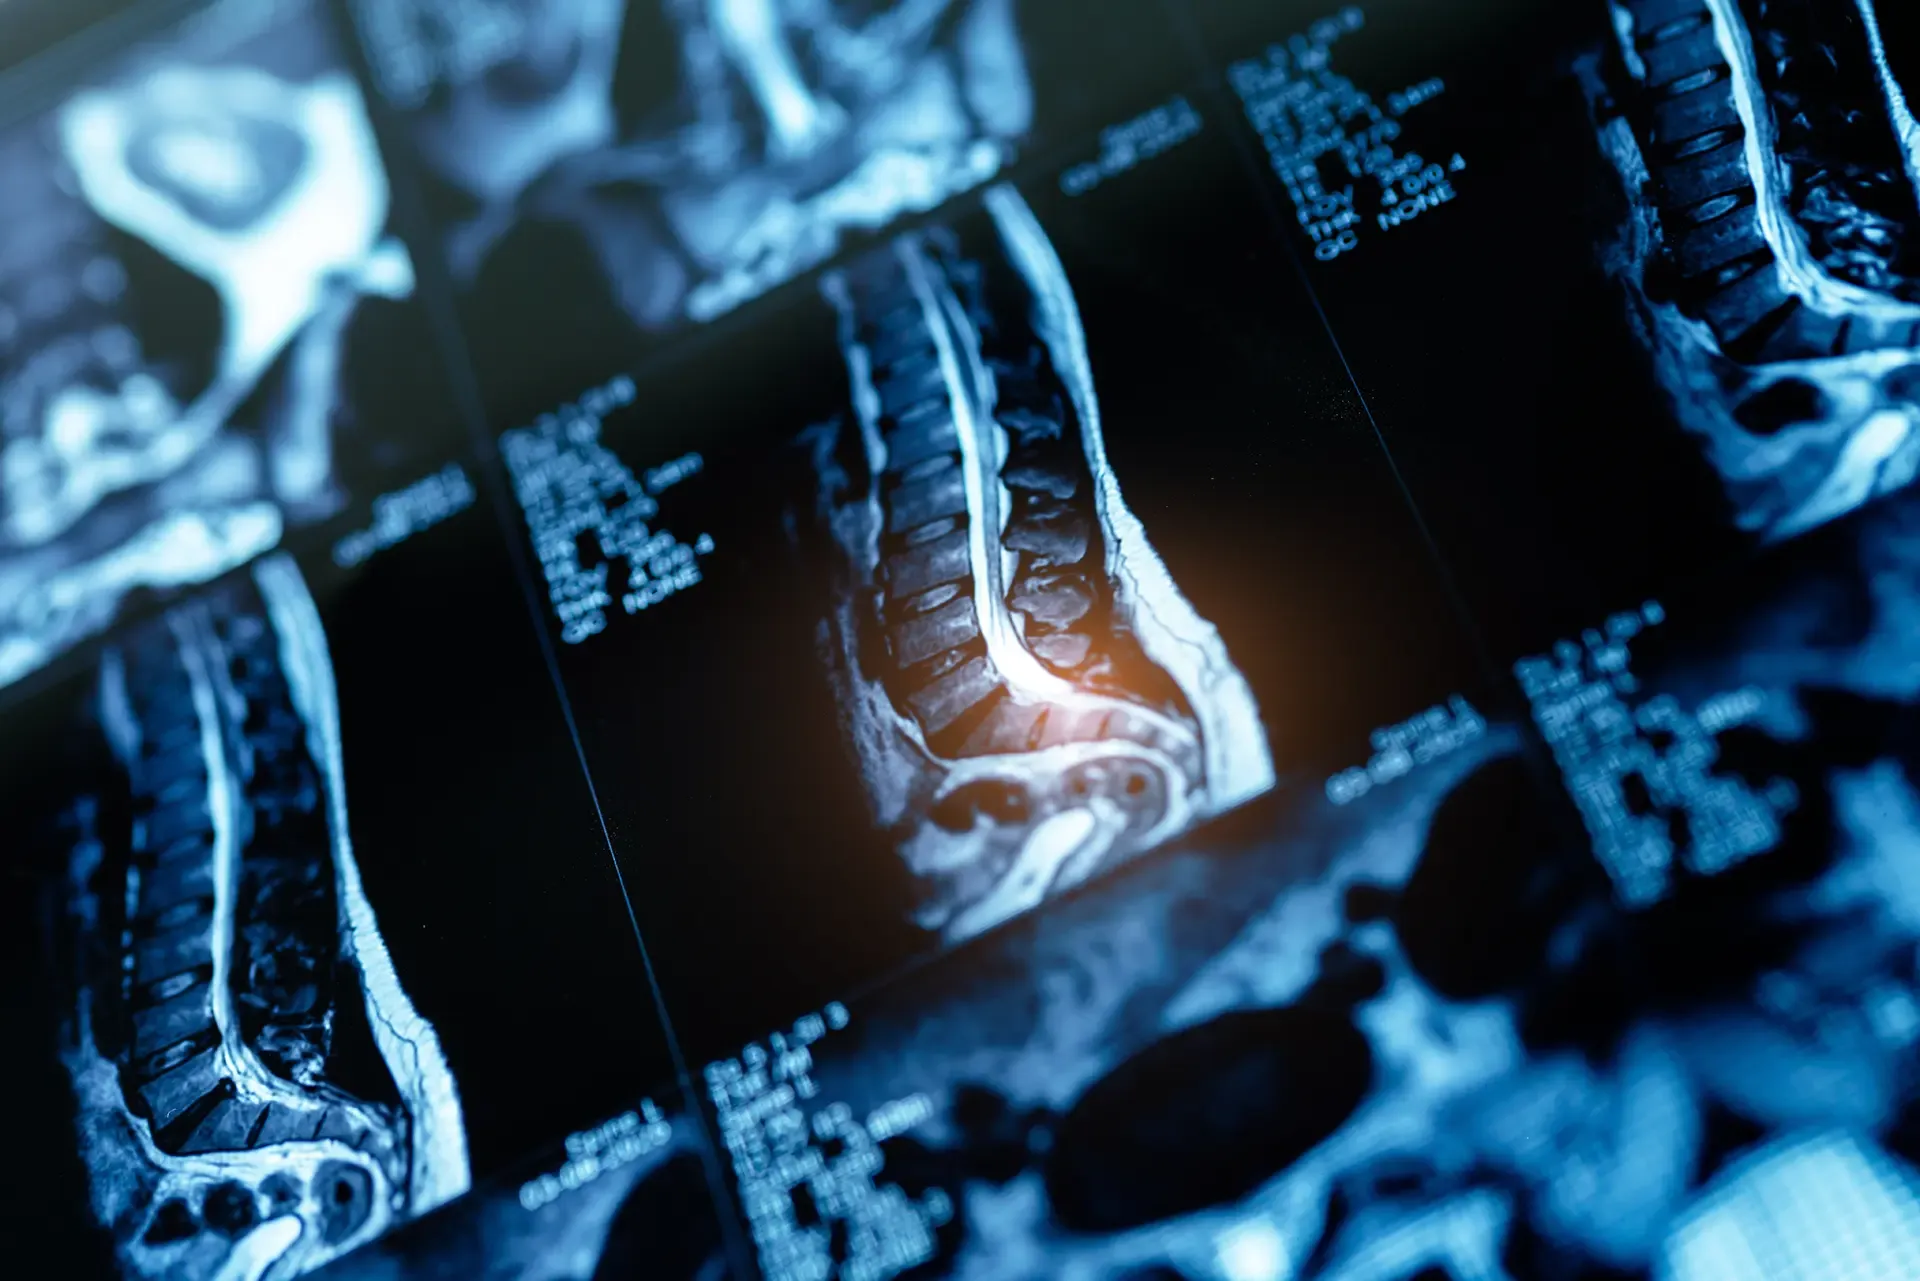

There are many risks of severe, debilitating injury after a serious car accident. Injury to the spinal cord is one of the most serious injuries that a person can sustain in a motor vehicle accident, and can be one of the most costly to not only treat. Not only will a spinal cord injury most likely require a long hospital stay and oftentimes surgery, it will usually also require that the patient take physical therapy for several months to come, and sometimes for life. This is because a spinal cord injury affects the brain’s ability to transport messages to all parts of the body. Many spinal cord injuries result in a complete loss of sensation and mobility below where the injury occurred. The group most at risk for spinal cord injury are young men between the ages of 15 and 35 who were otherwise healthy at the time of trauma.

Spinal cord injuries occur when there is a blunt trauma to the spinal cord, or when one or more vertebrae are crushed or compressed. Motor vehicle accidents are the number one cause of spinal cord injuries in the United States, accounting for 35 percent of such injuries annually. The types of spinal cord injury that result from motor vehicle accidents also tend to be among the most severe of this type of injury.

According to data compiled by the University of Washington and reported by the National Highway Traffic and Safety Administration, the most common level of spinal cord injury sustained in a motor vehicle is complete tetra: the complete loss of both arms and legs. The complete loss of use of either one’s arms or legs is the next most common level of spinal cord injury that results from a motor vehicle accident. Approximately 50 percent of patients who suffer a spinal cord injury in a motor vehicle accident have some impairment of both upper and lower limbs.